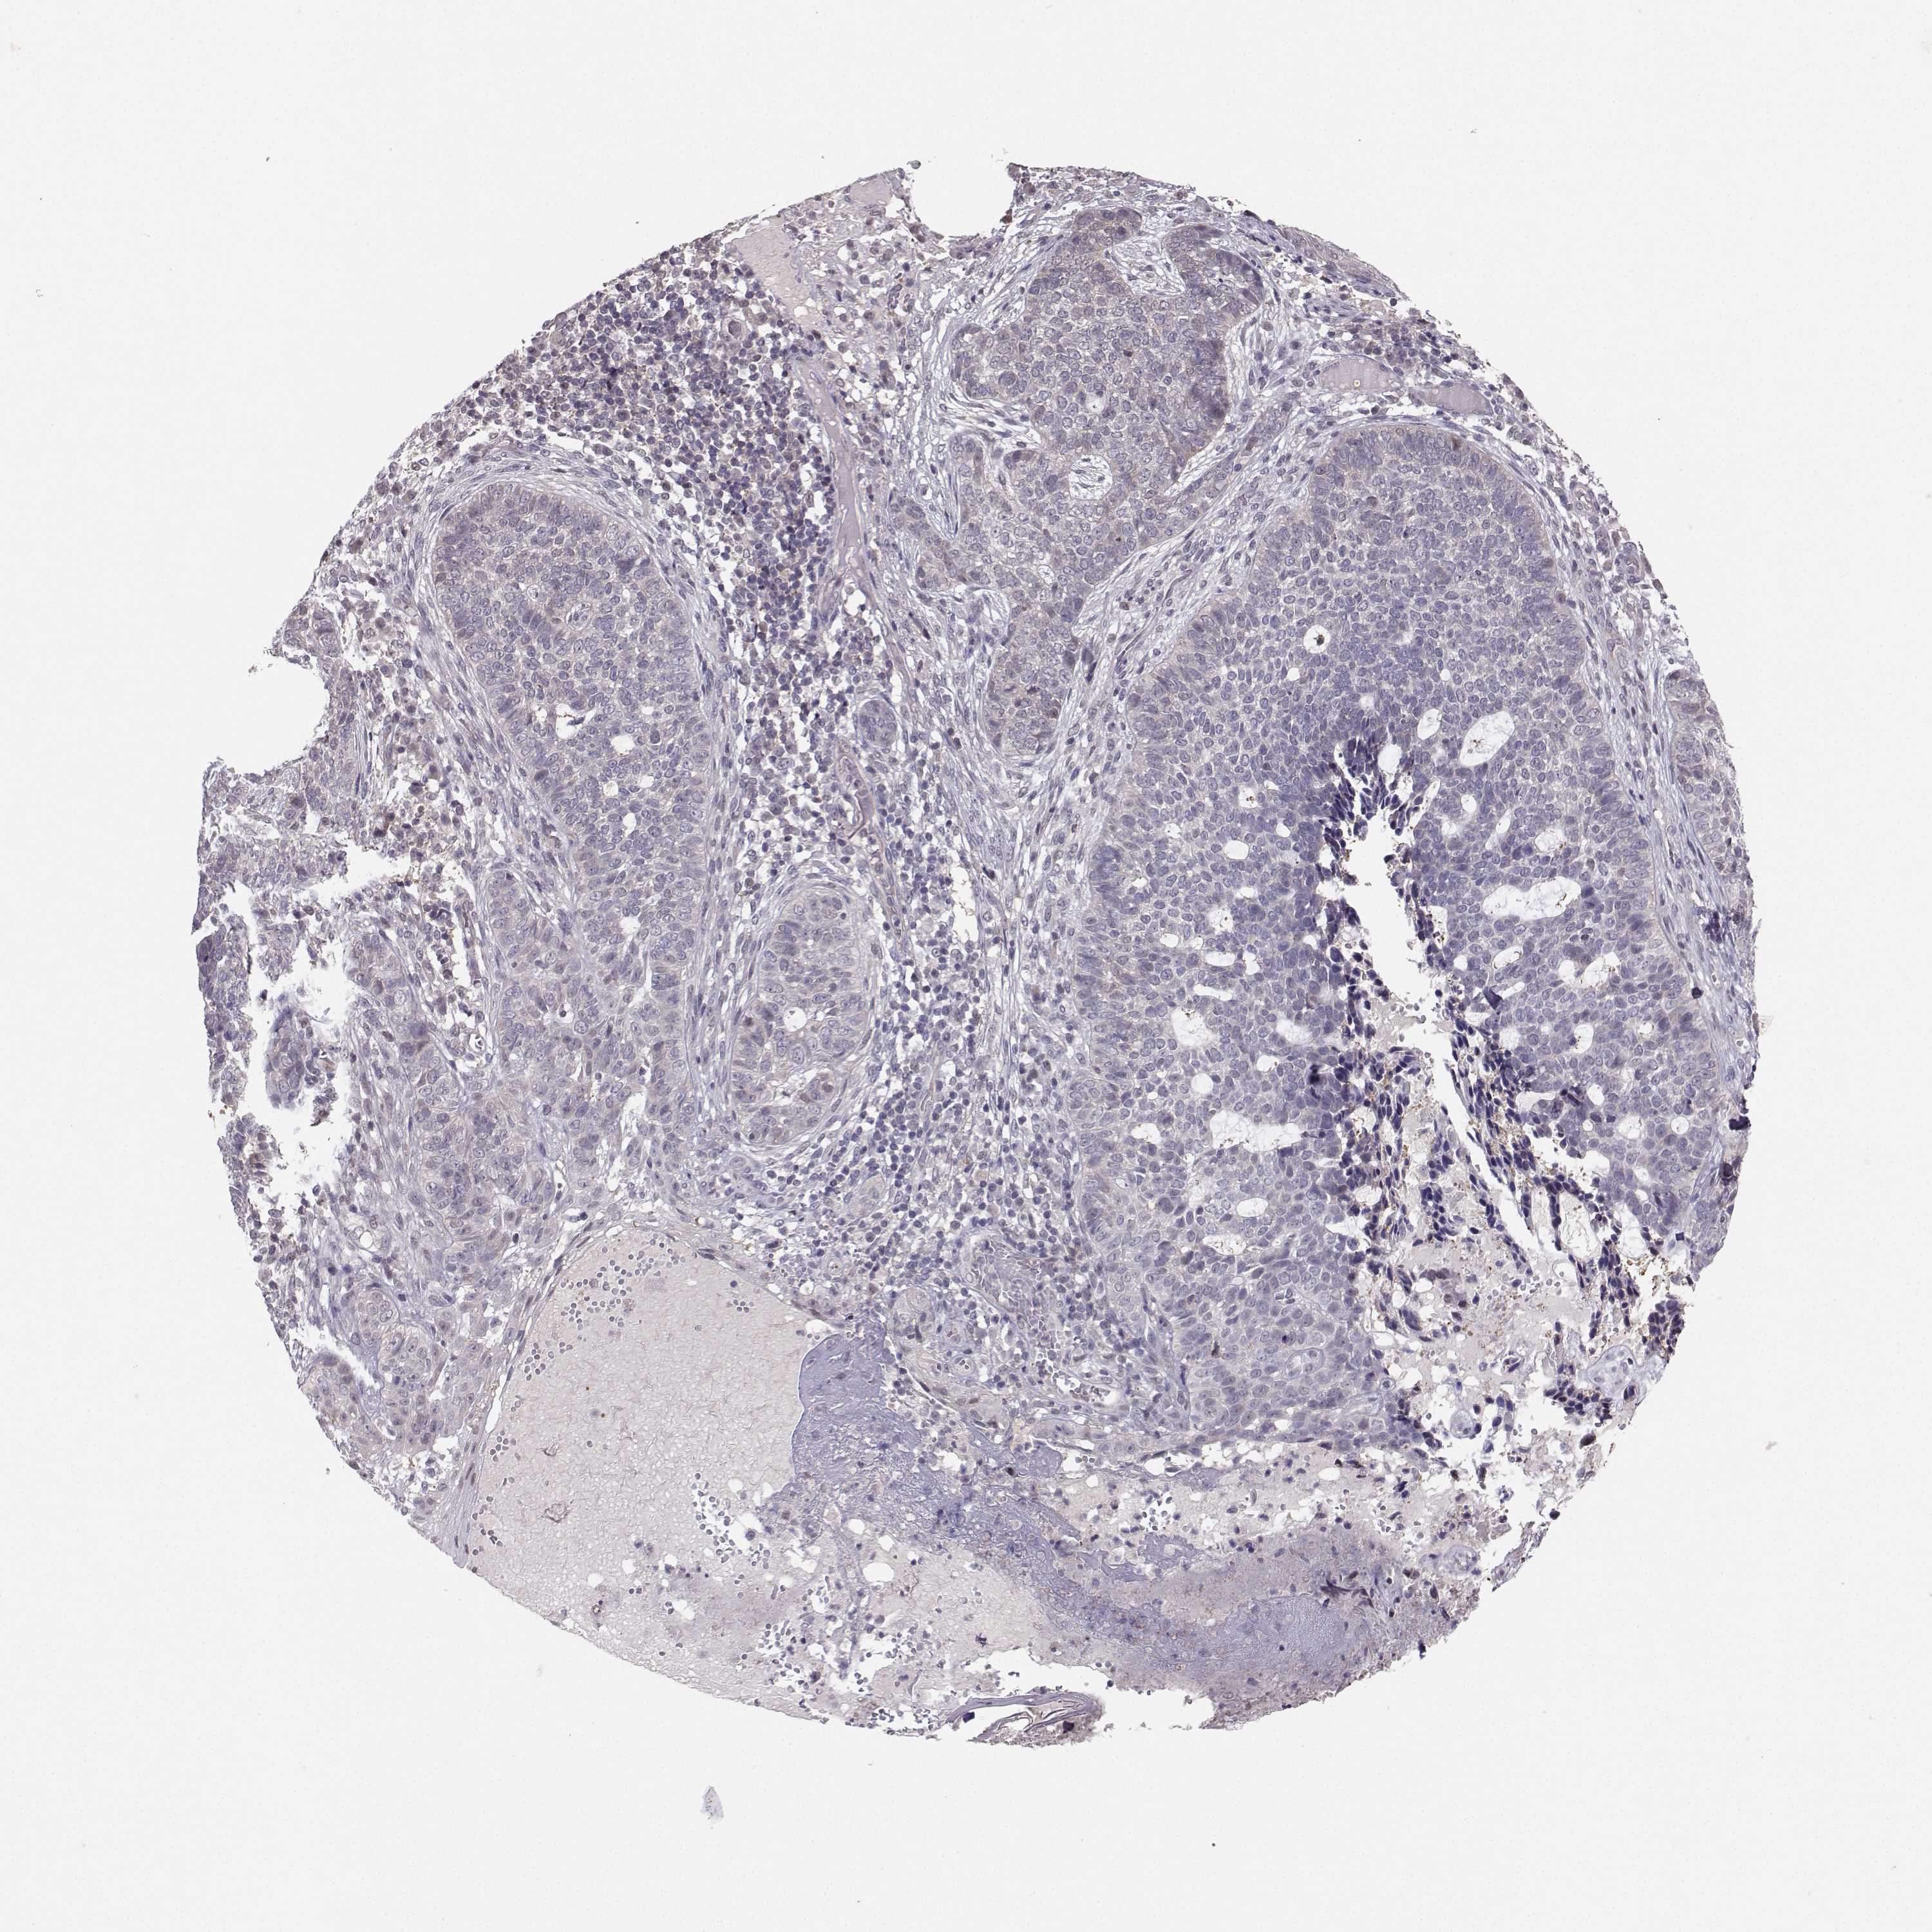

Basal cell and squamous cell cancer

SKIN CANCER - Protein expressioni

A mouse-over function shows sample information and annotation data. Click on an image to view it in a full screen mode. Samples can be filtered based on level of antibody staining by selecting one or several of the following categories: high, medium, low and not detected. The assay and annotation is described here.

Each image is clickable and will lead to virtual microscopy that enables deeper exploration of all samples and also displays staining intensity scores, fraction scores and subcellular localization as well as patient and tissue information for each sample.

Antibody CAB037336

Squamous cell carcinoma, NOS